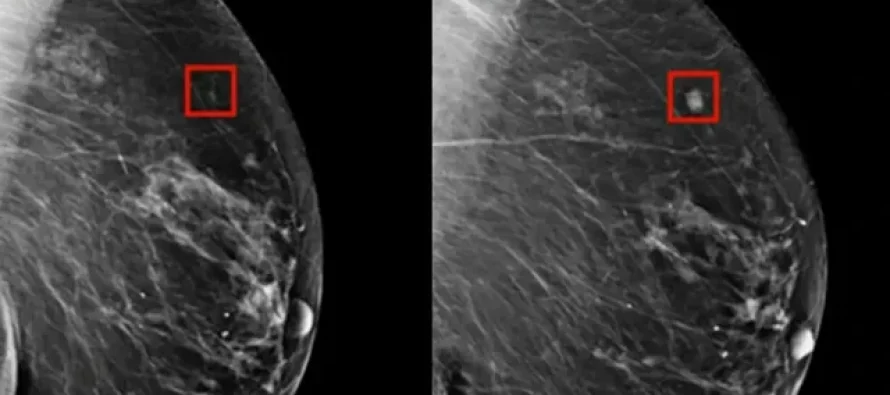

Një program i ‘AI’ zbuloi me sukses kancerin e gjirit tek një grua katër vjet përpara se të zhvillohej.

‘AI’ tani po përdoret në shqyrtimin e kancerit për të identifikuar problemet e mundshme shumë kohë përpara se ato të bëhen të dëmshme.

Dr. Larry Norton i Qendrës së Gjirit Lauder shpjegoi për CNN se ‘AI’, e cila ka ekzistuar që nga fundi i viteve 1990, po bëhet më e dobishme në identifikimin e problemeve të mundshme shëndetësore. AI mund të ndihmojë radiologët duke identifikuar zonat në mamografi që kanë nevojë për ekzaminim më të afërt.

Sidoqoftë, AI ka për qëllim të ndihmojë, jo të zëvendësojë, profesionistët e mjekësisë njerëzore. Mund të zvogëlojë ngarkesën e punës së radiologëve me 30% dhe të rrisë shkallët e zbulimit të kancerit me 13%, sipas New York Times. AI është përdorur gjithashtu me sukses për të zbuluar kancerin e mushkërive